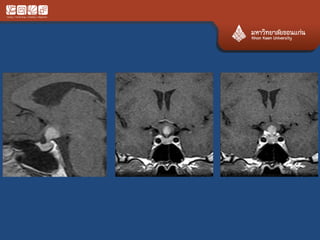

# chordoma

• Locally agreesive never metas

• Clivus, upper C, lower L, sacrum

• 70% at the midline

• Expansile, calcification, bright T2

• Ddx chondrosarcoma

• #meningioma with hyperostosis

• The larger part signal drop on T1FS+Gd  fat

marrow of the bone